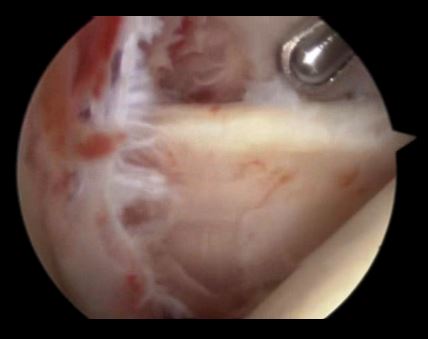

关节镜下可以彻底的清理关节内炎性滑膜组织及黏连带(盂肱关节及肩峰下关节)

清理后 ,肌腱活动度明显改善